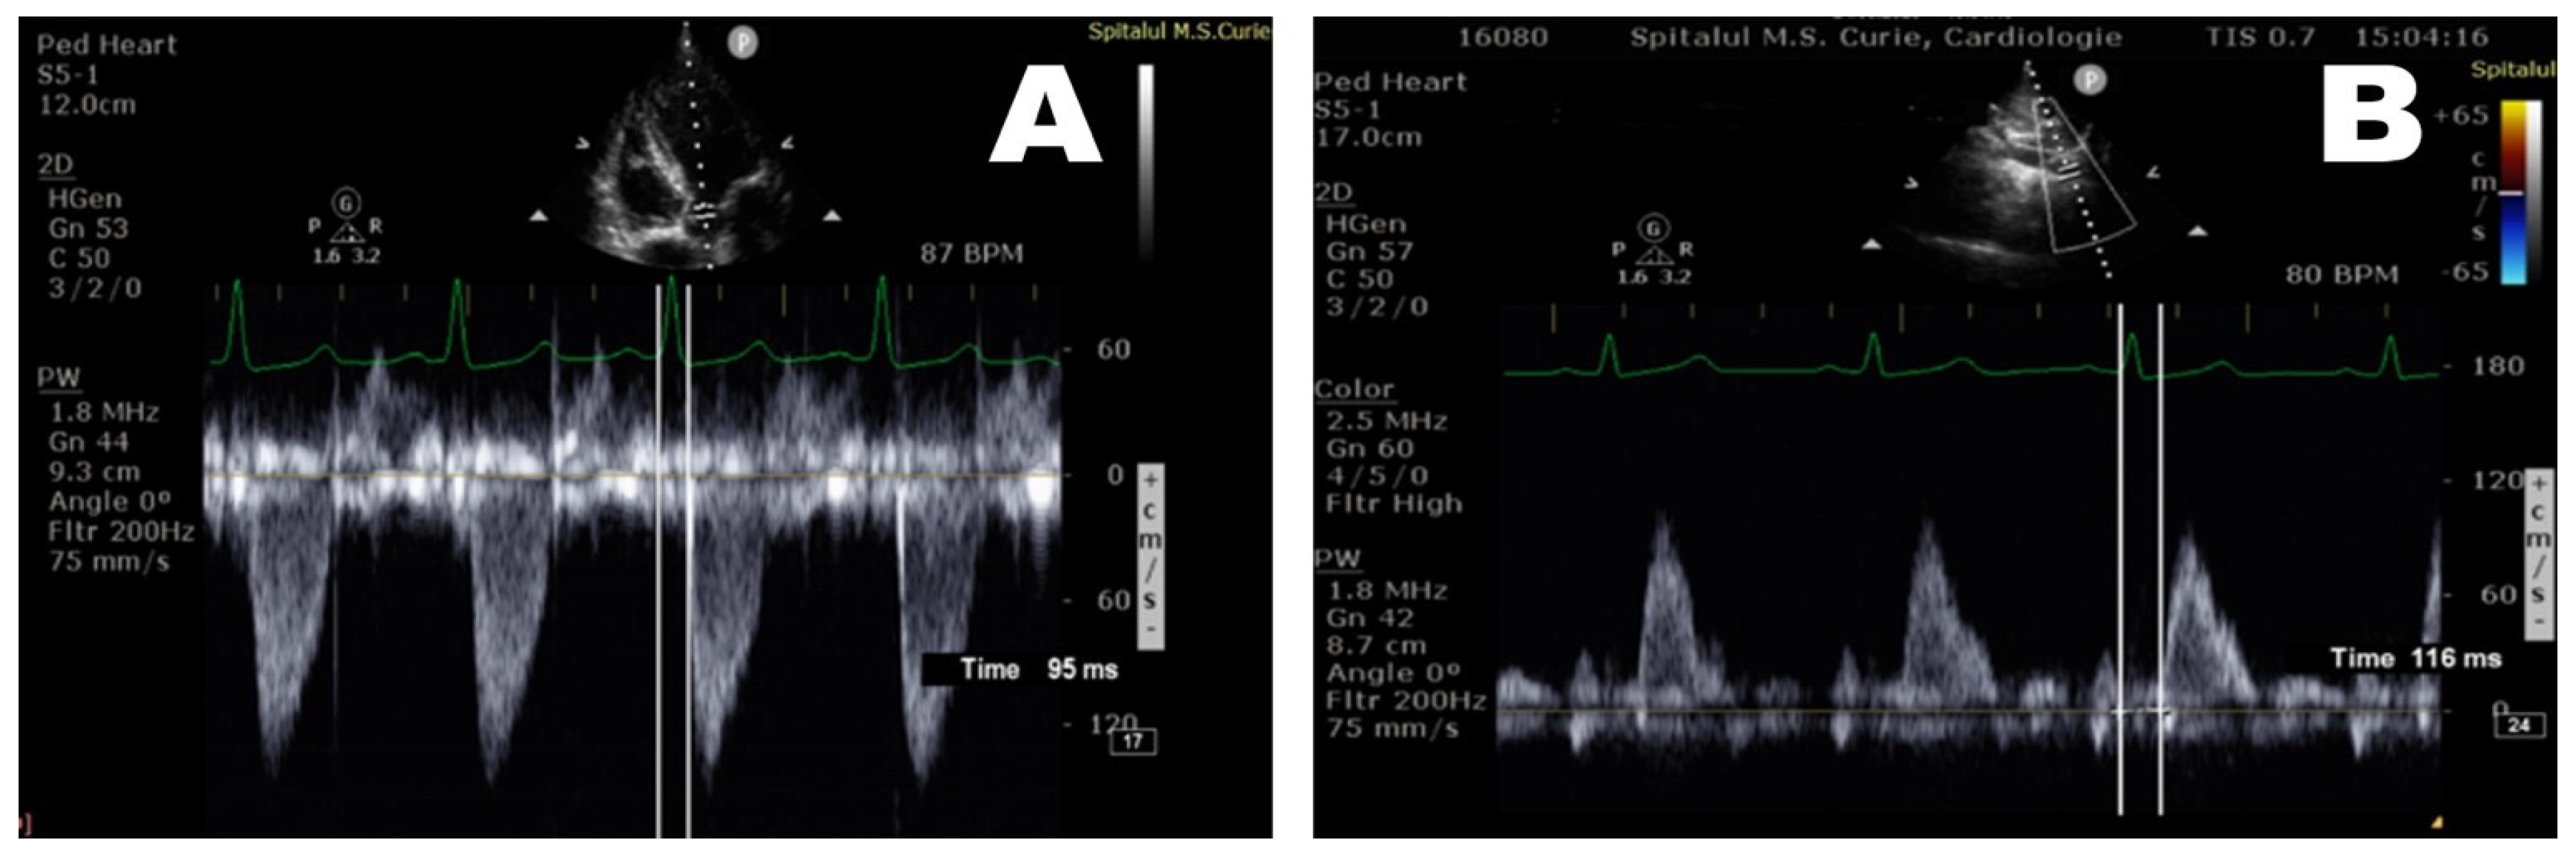

| T0(QRS—AoV) (msec) | 70 [63.9;80.1] | 65.7 [63.75;72] | 74.47 [60;92] | 72 [64;80] |

| T1(QRS—AscAo) (msec) | 75 [67;84] | 70.8 [69.75;75.25] | 80.18 [66;97.5] | 76.6 [67;84] |

| T2(QRS –DescAo) (msec) | 109 [98.9;117.1] | 107.3 [104.3;115] | 118.8 [101;136] | 104 [92;113] |

| PWV—AscAo (m/sec) ** | 4 [3.3;4] | 3.65 [3.3;4] | 3.44 [3.3; 4] | 4.53 [4; 6.92] |

| PWV—DescAo (m/sec) *** | 4.05 [3.61;4.75] | 3.795 [3.58;4.39] | 3.73 [3.46;4.015] | 5.279 [4.64;5.83] |